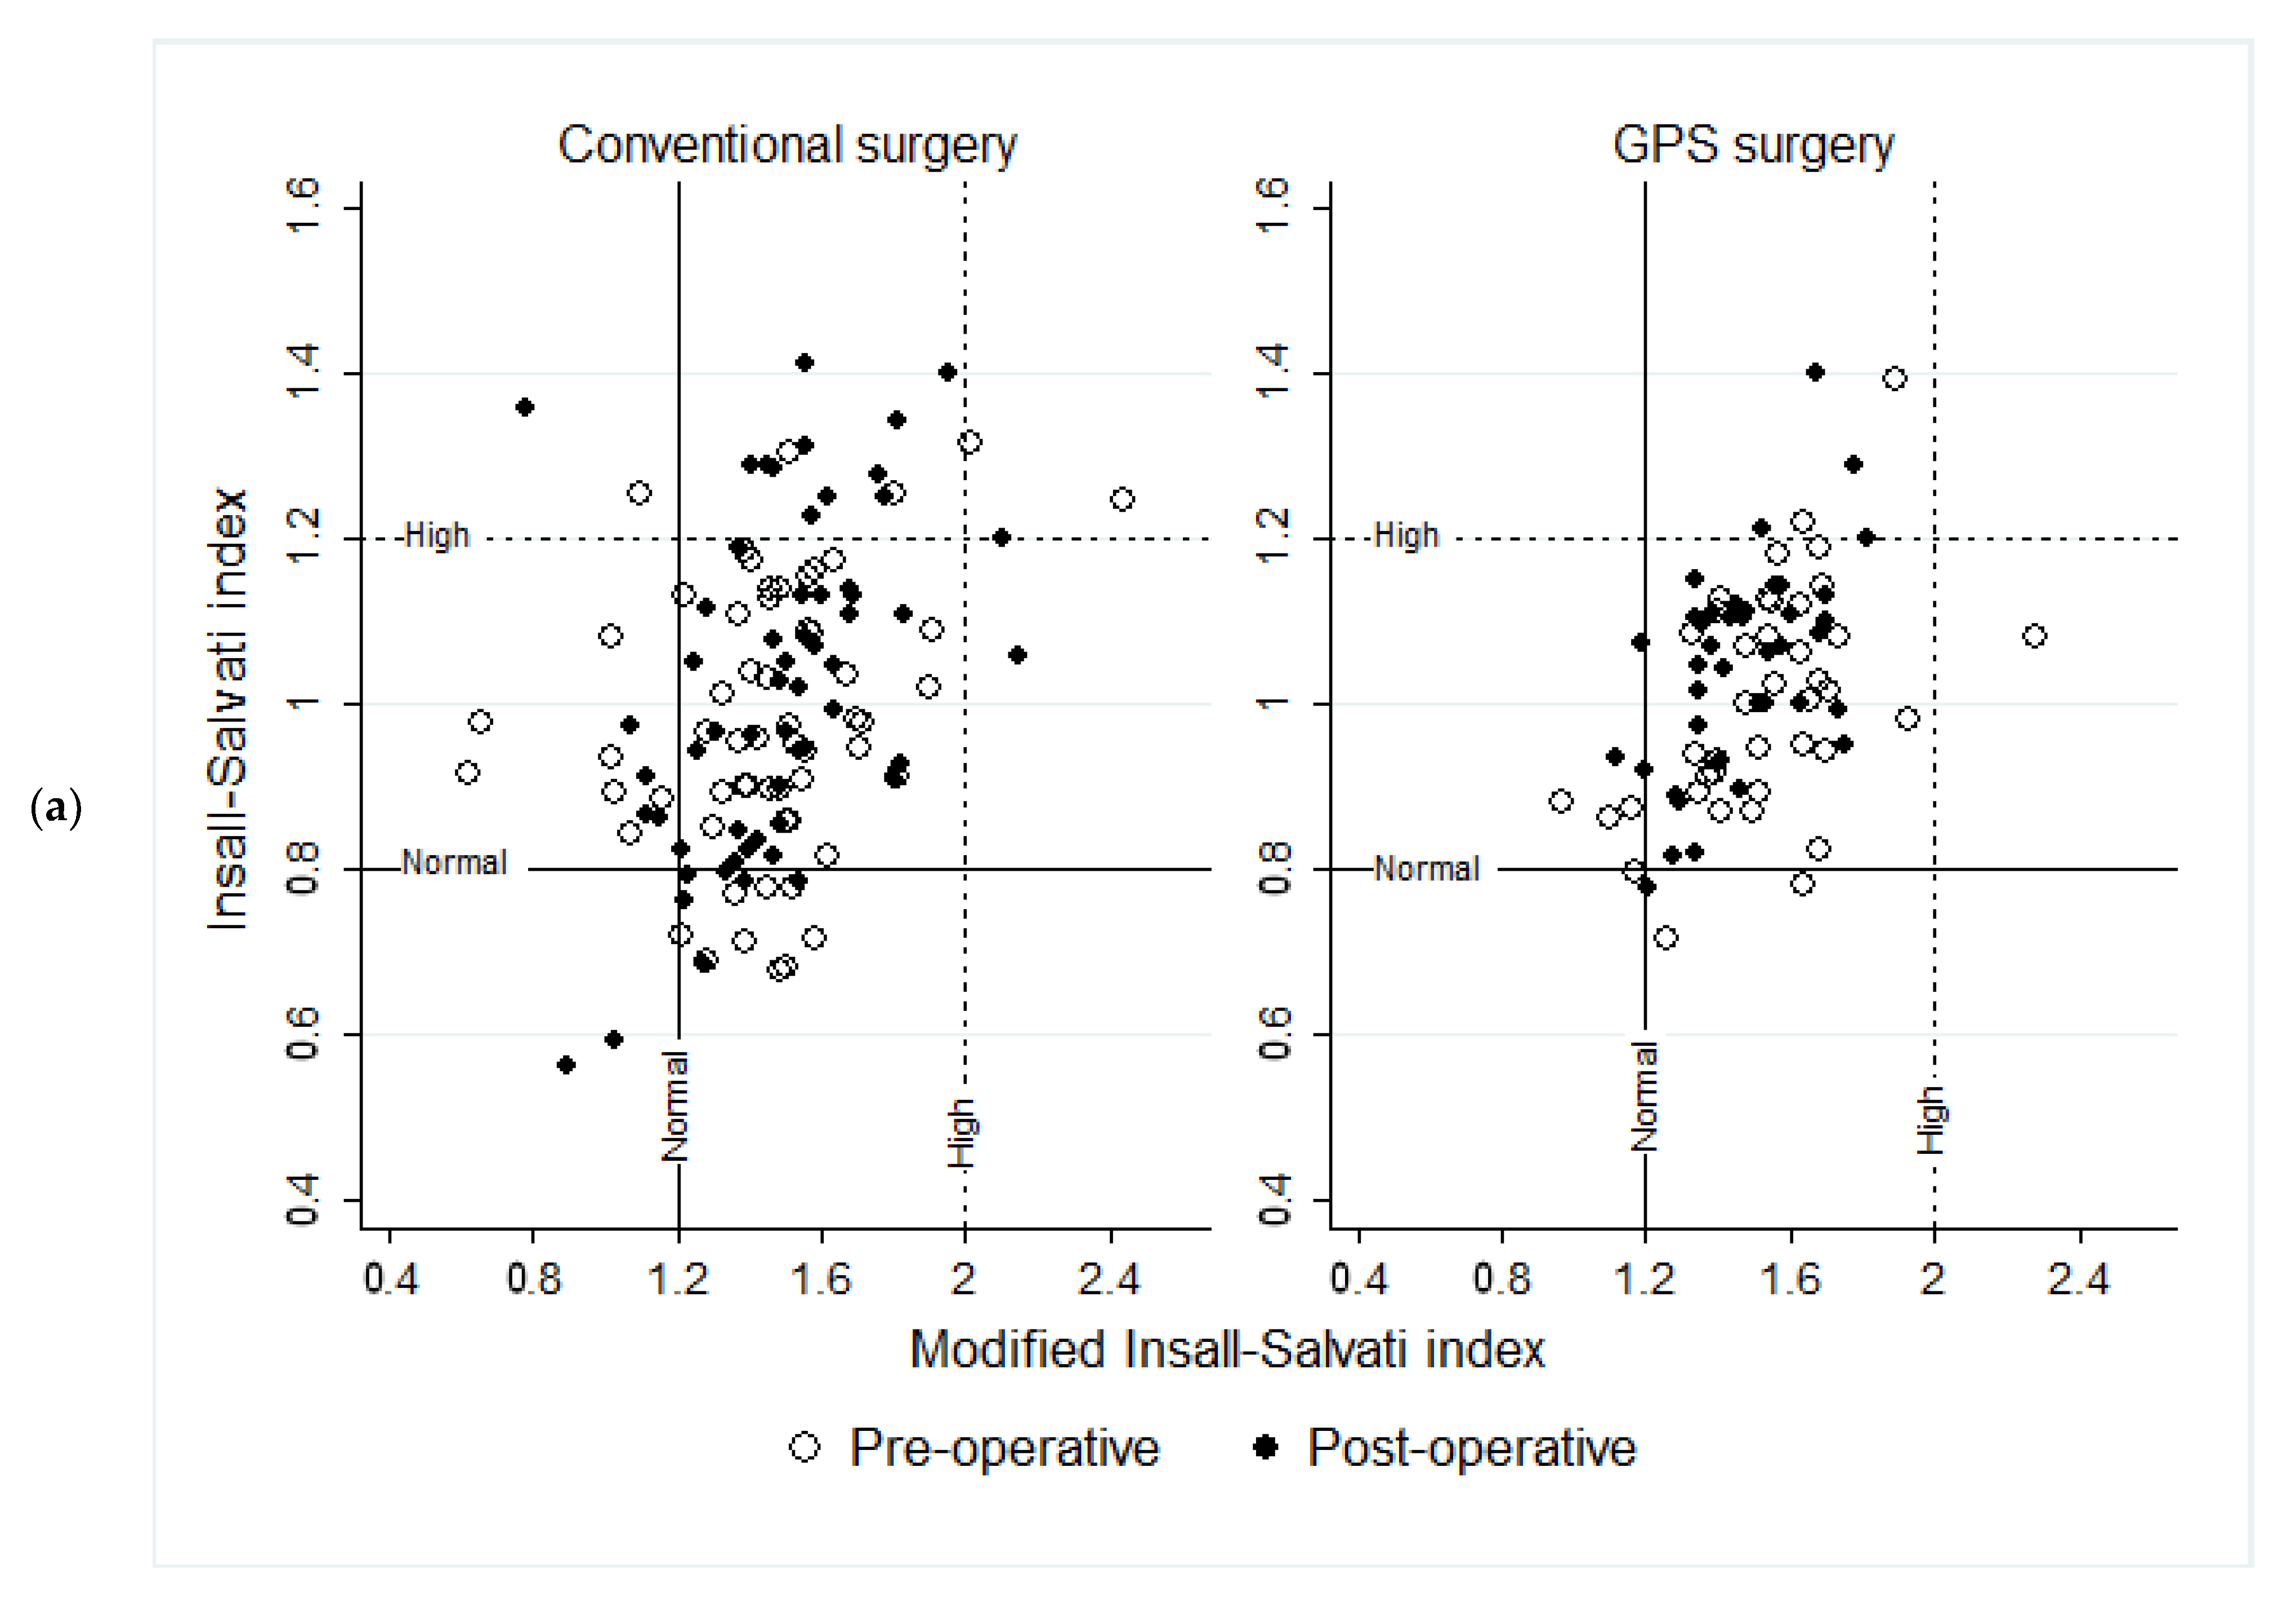

- The patellar height was evaluated with the Insall–Salvati index—IS (<0.8 low, 0.8–1.2 normal, >1.2 high), Insall–Salvati modified index—ISm (>2 high, 1.2–2.1 normal), the Caton–Deschamps index—CD (<0.6 low, 0.6–1.2 normal, >1.2 high), and the Blackburne–Peel index—BP (<0.5 low, 0.5–1 normal, >1 high) [15].

| Index | Measure Time | Conventional Surgery n = 59 (Mean ± SD) | GPS Surgery n = 41 (Mean ± SD) | Mean Comparison, by Surgery | Variance Comparison, by Surgery |

| IS | Pre-Operative | 0.98 ± 0.2 | 0.99 ± 0.1 | p = 0.501 t | p = 0.237 f |

| Post-Operative | 1.02 ± 0.2 | 1.04 ± 0.1 | p = 0.431 t | p = 0.002 f | |

| Pre-Post mean comparison | p = 0.031 pt | p = 0.008 pt | |||

| Pre-Post variance comparison | p = 0.119 f | p = 0.596 f | |||

| ISm | Pre-Operative | 1.45 ± 0.3 | 1.52 ± 0.2 | p = 0.157 z | p = 0.561 w |

| Post-Operative | 1.48 ± 0.3 | 1.47 ± 0.2 | p = 0.842 t | p = 0.008 f | |

| Pre-Post mean comparison | p = 0.632 pt | p = 0.199 pt | |||

| Pre-Post variance comparison | p = 0.977 w | p = 0.067 f | |||

| CD | Pre-Operative | 0.83 ± 0.2 | 0.84 ± 0.2 | p = 0.472 z | p = 0.685 w |

| Post-Operative | 0.72 ± 0.2 | 0.77 ± 0.1 | p = 0.183 t | p = 0.011 f | |

| Pre-Post mean comparison | p = 0.000 pt | p = 0.011 pt | |||

| Pre-Post variance comparison | p = 0.023 w | p = 0.333 f | |||

| BP | Pre-Operative | 0.75 ± 0.2 | 0.77 ± 0.2 | p = 0.314 z | p = 0.575 w |

| Post-Operative | 0.69 ± 0.2 | 0.75 ± 0.1 | p = 0.099 t | p = 0.011 f | |

| Pre-Post mean comparison | p = 0.043 pt | p = 0.295 pt | |||

| Pre-Post variance comparison | p = 0.074 w | p = 0.584 f |